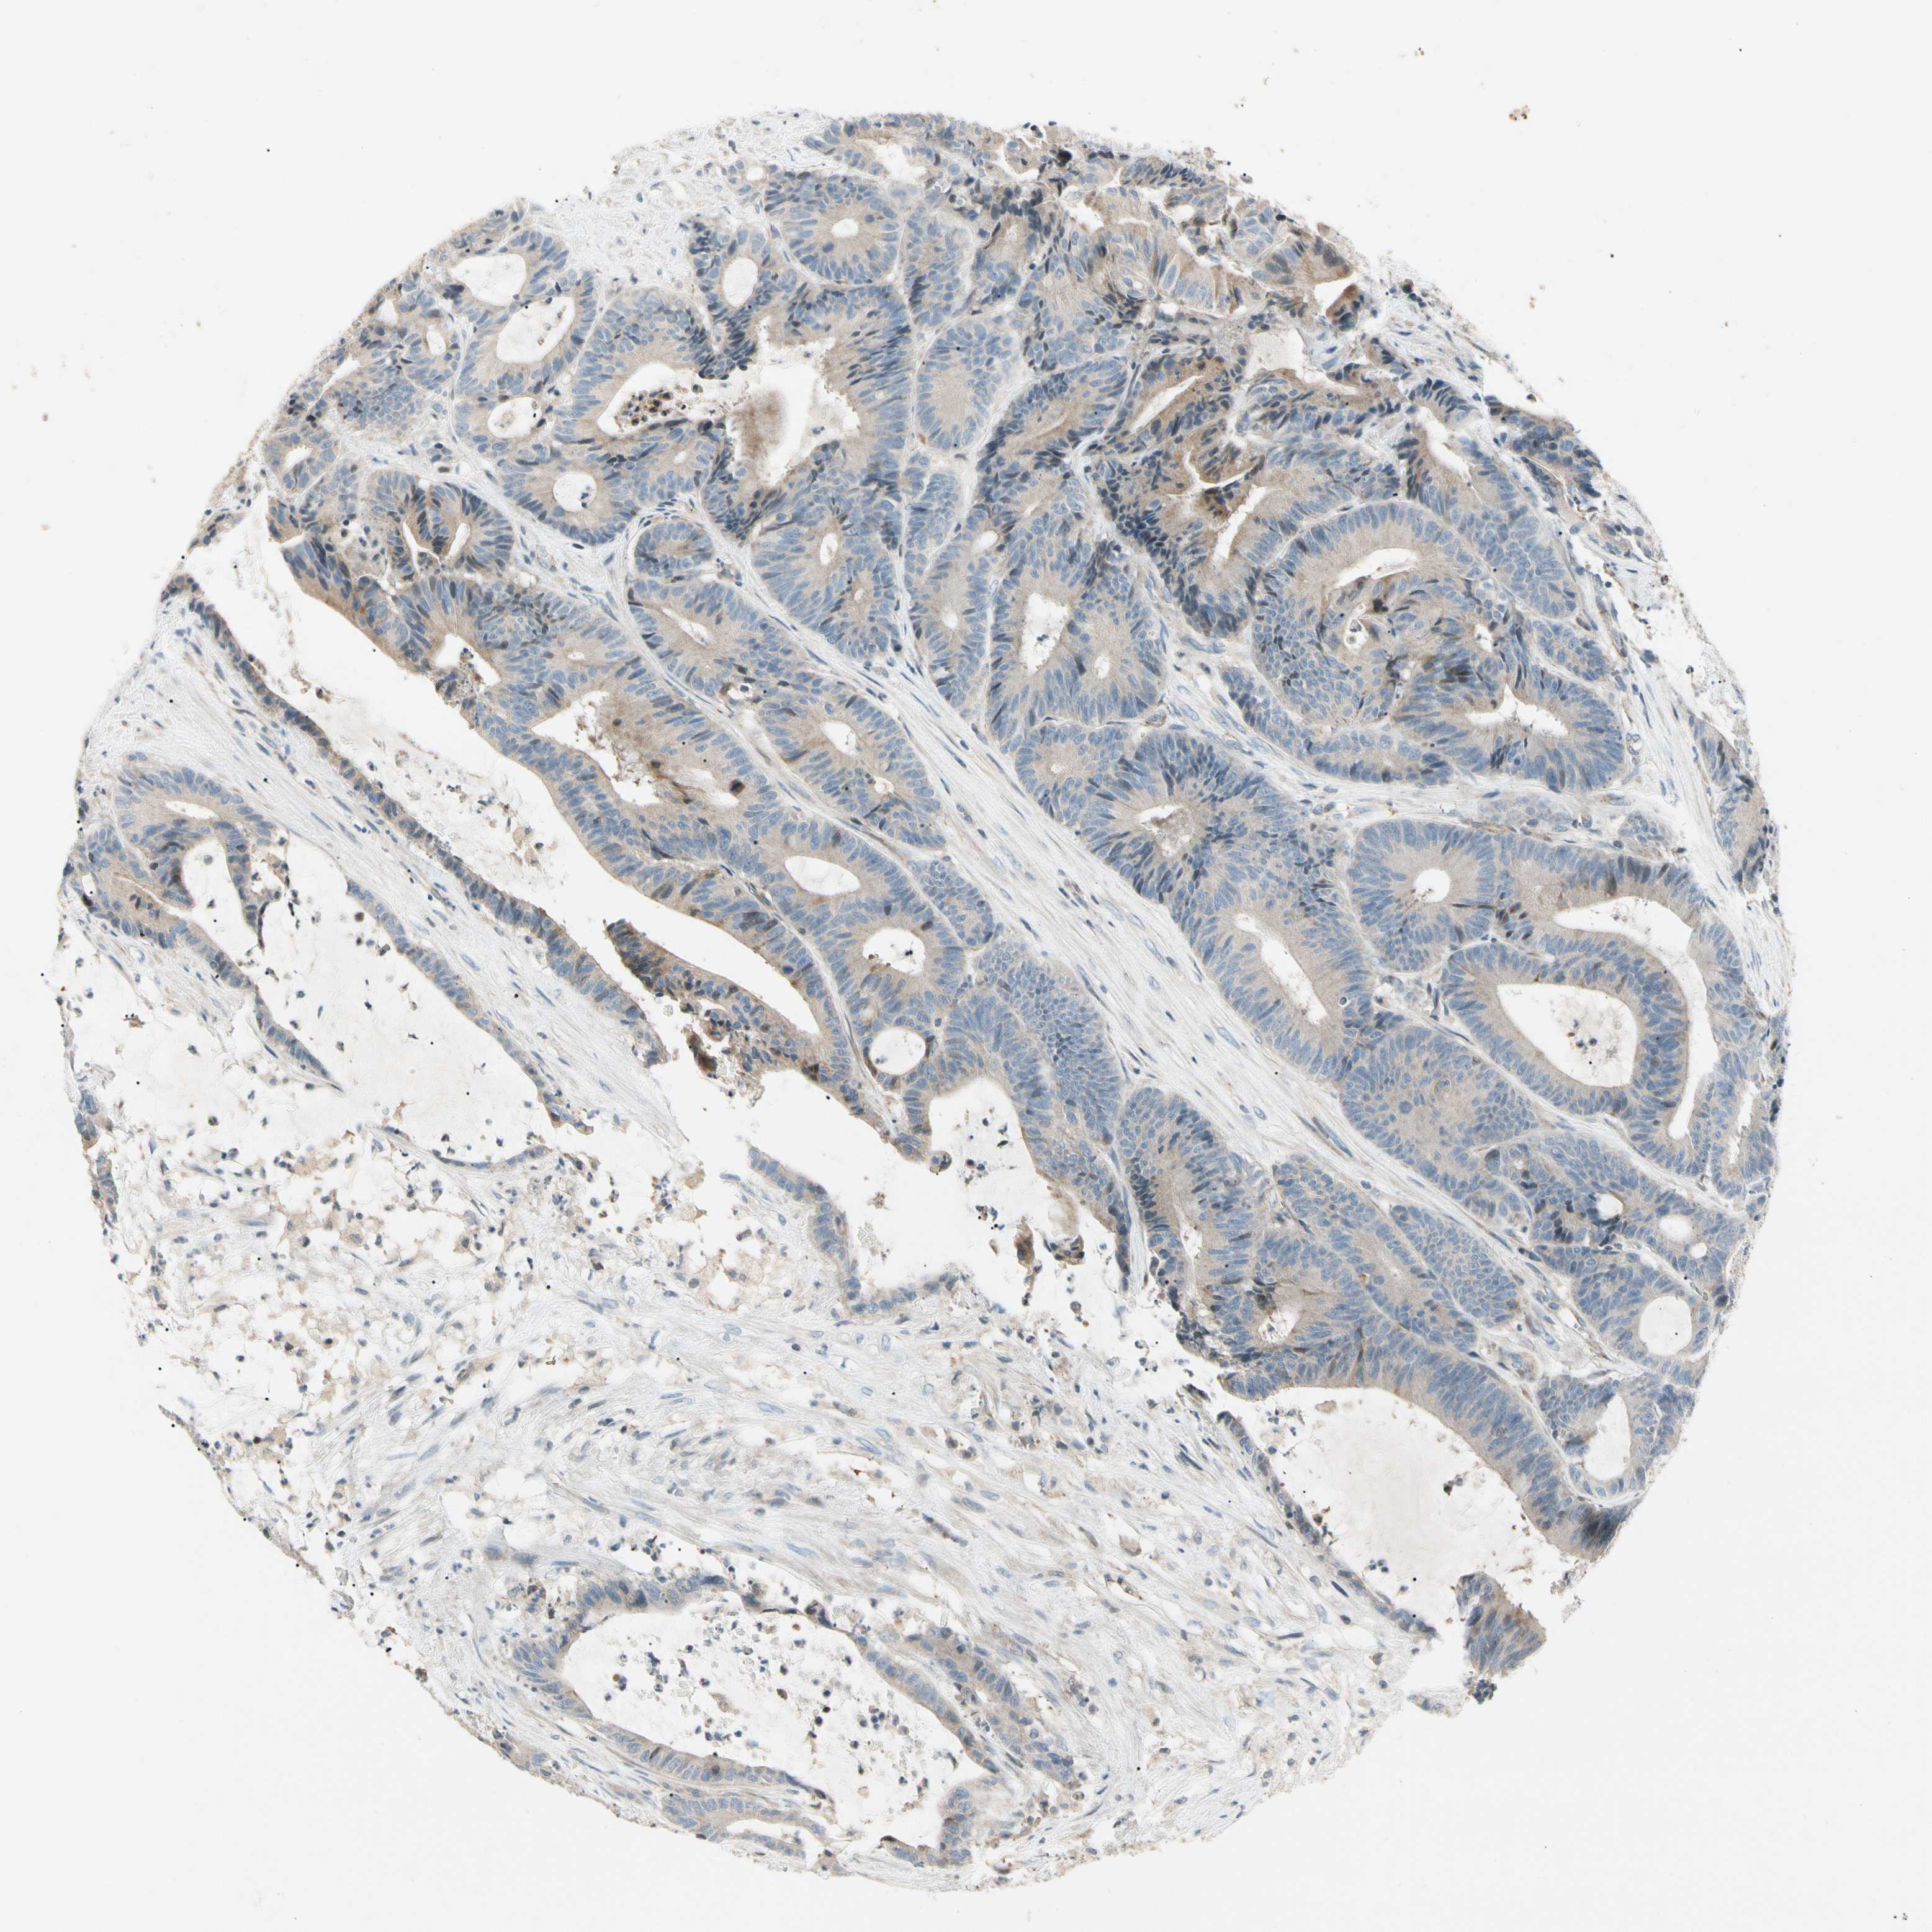

RECTUM ADENOCARCINOMA (TCGA) - Interactive survival scatter ploti

The Survival Scatter plot shows the clinical status (i.e. dead or alive) for all individuals in the patient cohort, based on the same data that underlies the corresponding Kaplan-Meier plots. Patients that are alive at last time for follow-up are shown in blue and patients who have died during the study are shown in red.

The x-axis shows the expression levels (FPKM) of the investigated gene in the tumor tissue at the time of diagnosis. The y-axis shows the follow-up time after diagnosis (years). Both axes are complimented with kernel density curves demonstrating the data density over the axes. The top density plot shows the expression levels (FPKM) distribution among dead (red) and alive patients (blue). The right density plot shows the data density of the survived years of dead patients with high and low expression levels respectively, stratified using the cutoff indicated by the vertical dashed line through the Survival Scatter plot. This cutoff is automatically defined based on the FPKM cutoff that minimizes the p-score. The cutoff can be changed by dragging the vertical line or by entering a cutoff value in the square labeled "Current cut-off".

Under the Survival Scatter plot the p-score landscape (black curve; left axis) is shown together with dead median separation (red curve; right axis). Dead median separation is the difference in median mRNA expression between patients who have died with high and low expression, respectively. It is calculated as follows: median FPKM expression of dead patients with high expression - median FPKM expression of dead patients with low expression. This is intended to aid the user in visually exploring custom cutoffs and the associated p-scores and dead median separation.

Individual patient data is displayed and can be filtered by clicking on one or more of the category buttons on the top of the page. Categories describing expression level and patient information include: high, low, alive, dead, female, male and tumor stages. The scale of the x-axis can be toggled between linear and log-scale by clicking on the "x log" button. Mouse-over function shows TCGA ID, patient information and mRNA expression (FPKM) for each patient.

& Survival analysisi

Kaplan-Meier plots summarize results from analysis of correlation between mRNA expression level and patient survival. Patients were divided based on level of expression into one of the two groups "low" (under cut off) or "high" (over cut off). X-axis shows time for survival (years) and y-axis shows the probability of survival, where 1.0 corresponds to 100 percent.

CDH6 is not prognostic in Rectum Adenocarcinoma (TCGA)

Best expression cut offi

Based on the FPKM value of each gene, patients were classified into two groups and association between prognosis (survival) and gene expression (FPKM) was examined. The best expression cut-off refers the FPKM value that yields maximal difference with regard to survival between the two groups at the lowest log-rank P-value. Best expression cut-off was selected based on survival analysis .

When clicking on this number, the vertical dashed line indicating cut-off, the interactive survival plot, and the Kaplan-Meier curve will be adjusted to show results based on the best expression cut-off.

: 1.13

Median expressioni

Median expression refers to the median FPKM value calculated based on the gene expression (FPKM) data from all patients in this dataset. When clicking on this number, the vertical dashed line indicating cut-off, the interactive survival plot, and the Kaplan-Meier curve will be adjusted to show results based on the median expression.

: N/A

P scorei

Log-rank P value for Kaplan-Meier plot showing results from analysis of correlation between mRNA expression level and patient survival.

N/A

5-year survival highi

5-year survival for patients with higher expression than the expression cutoff.

For melanoma and glioma, 3-year survival is shown.

5-year survival lowi

5-year survival for patients with lower expression than the expression cutoff.

TCGA RNA samplesi

RNA-seq data is reported as average FPKM (number Fragments Per Kilobase of exon per Million reads), generated by the The Cancer Genome Atlas (TCGA) .

Normal distribution across the dataset is visualized with box plots, shown as median and 25th and 75th percentiles. Points are displayed as outliers if they are above or below 1.5 times the interquartile range. FPKM values of the individual samples are presented next to the box plot.

Average pTPM 1.0

Number of samples 88